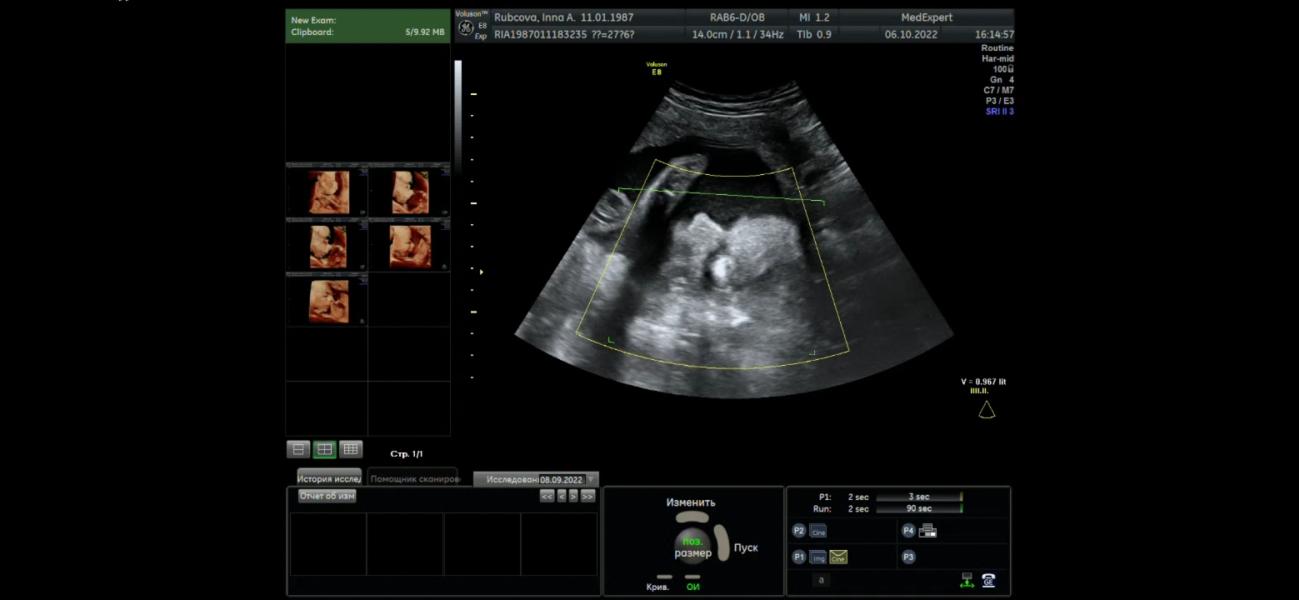

Девочки у кого сколько детки весили в 27-28 нед. И сильно ли отличались акушерская ПДР от ПДР по УЗИ? Напрягло ещё обвитие пуповиной 🤨. Нам сегодня 27нед.и 6 дней

На УЗИ разглядели🧐 однократно обвитие, нервные клетки зашевелились🙄